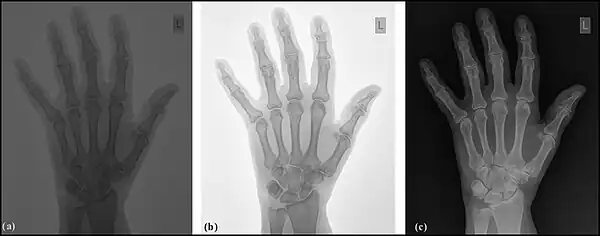

Image sampling is the process used to digitise the spatial information in an image. It is typically achieved by dividing an image into a square or rectangular array of sampling points - see the following figure. Each of the sampling points is referred to as a picture element - or pixel to use computer jargon. Although in the context of DR image receptors, the term detector element, or del, is also used. Naturally, the larger the number of pixels or dels, the closer the spatial resolution of the digitised image approximates that of the radiation pattern transmitted through the patient – see the following figure, panels (a) and (b).

The process may be summarised as the digitisation of an image into an N x N array of pixel data. Examples of values for N are 1024 for a angiography image, and 3,000 for a digital radiograph.

Note that each pixel represents not a point in the image but rather an element of a discrete matrix. Distance along the horizontal and vertical axes is no longer continuous, but instead proceeds in discrete steps, each given by the pixel size. With larger pixels, not only is the spatial resolution poor, since there is no detail displayed within a pixel, but grey-level discontinuities also appear at the pixel boundaries (pixelation) - see panel (b) in the figure. The spatial resolution improves with smaller pixels and a perceived lack of pixelation gives the impression of a spatially continuous image to the viewer.

Image quantisation is the process used to digitise the brightness information in an image. It is typically achieved by representing the brightness of a pixel by an integer whose value is proportional to the brightness. This integer is referred to as a 'pixel value' and the range of possible pixel values which a system can handle is referred to as the grey scale. Naturally, the greater the grey scale, the closer the brightness information in the digitised image approximates that of the original image – see the following figure, panels (a) and (c). The process can be considered as the digitisation of image brightness into G shades of grey. The value of G is dependent on the binary nature of the information coding. Thus G is generally an integer power of 2, i.e. G=2m, where m is an integer which specifies the number of bits required for storage. Examples of values of G are 1,024 (m=10) in fluoroscopy, 2,048 (m=11) in angiography and 4,096 (m=12) in digital radiography. Note that the slight difference between the brightness in an analogue image and its pixel value in the digital image is referred to as the quantisation error, and is lower at larger values of G.